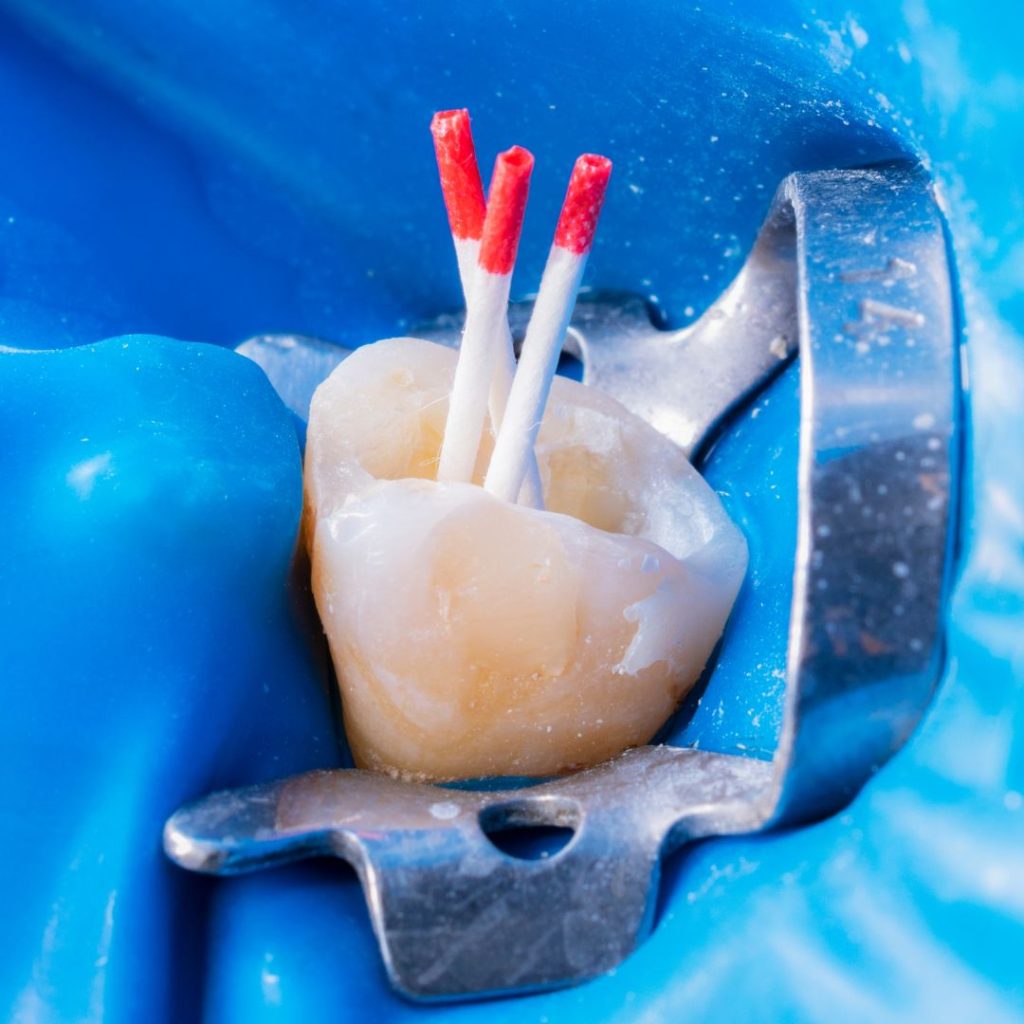

Klinik Galerimiz

Klinik ortamımızı ve tedavi süreçlerimizi yakından inceleyin